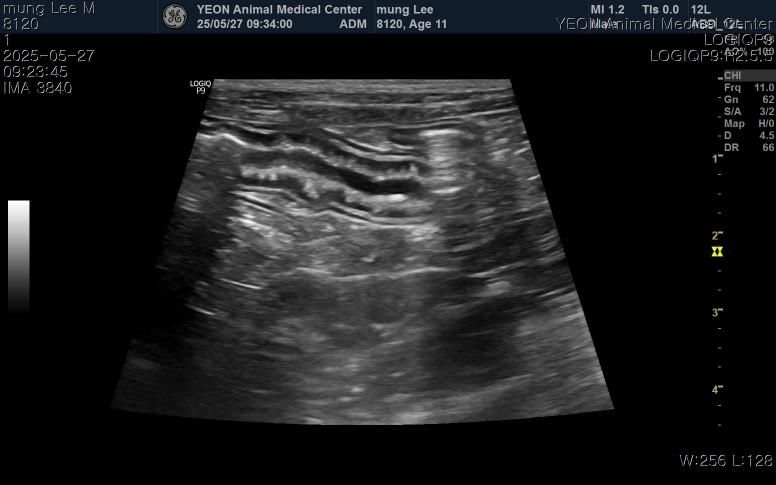

구토, 식욕저하, 기력저하로 내원해서 진료,검사 받아보니 염증, 간, 담낭 등 수치가 심하게 높다고 했고 빠른 입원치료와 담낭절제수술을 안내받았습니다.

그리고 십이지장에 크론병?도 의심된다고 하는데 담낭 치료와는 치료방법이 상극이어서 담낭 먼저 제거하고 스테로이드치료가 필요하다고 안내받았습니다.

담낭이 파열했을 가능성을 충분히 고려해야 하는 상태로 보이므로 비선택적 수술 즉, 반드시 수술해야 하는 상태 가능성이 높습니다. https://diamed.tistory.com/341 파열전에 수술하는것에 비해 사망 가능성이 높아진 상태이지만, 비선택적으로 반드시 수술해야 하는 상태로 판단됩니다. 주치의와 진솔한 대화 후 수술 진행하시기 바랍니다.